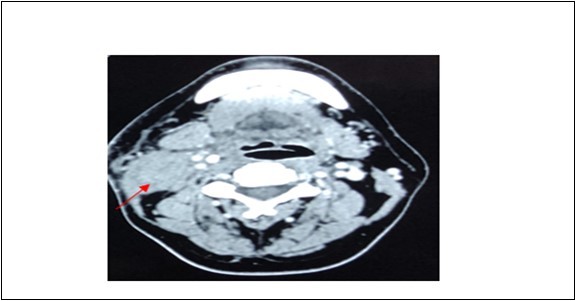

A 42-year-old gentleman, ex-smoker with underlying diabetes mellitus came to our clinic for right neck swelling for about 10 months. The swelling was gradually increasing in size and was giving occasional pain to the patient. But, there were no obstructive symptoms nor a history of prior exposure to radiation. Upon examination, there was a 2x2cm firm, fixed and non-tender swelling palpable at level II of right neck, with no skin changes seen. The facial nerve was intact and the oral cavity was clear. Proceed with flexible scope, there was no mass seen, and laryngeal structures were normal. Fine needle aspiration revealed normal salivary gland elements. A contrasted-CT scan reported a deep lobe parotid gland mass with non-opacification of the right internal jugular vein which could be from compression or thrombosis. [Figure 3] A wedge biopsy was performed subsequently which reported as squamous cell carcinoma, moderately-differentiated. [Figure 4, Figure 5 & Figure 6] Given the malignancy reported, a right total parotidectomy with right selective neck dissection was performed. Post-operatively, the patient developed House-Brackmann grade II facial nerve palsy. Histopathology showed evidence of squamous cell carcinoma with no involvement of adjacent nodes. A final diagnosis of T3N0M0 squamous cell carcinoma of the parotid gland was established. The patient was then referred to the oncology team for chemoradiation. Currently, the patient has completed adjuvant radiotherapy with no signs of recurrence observed so far at six months follow-up.

Figure 3.Contrasted CT neck showing mass at deep lobe of right parotid gland